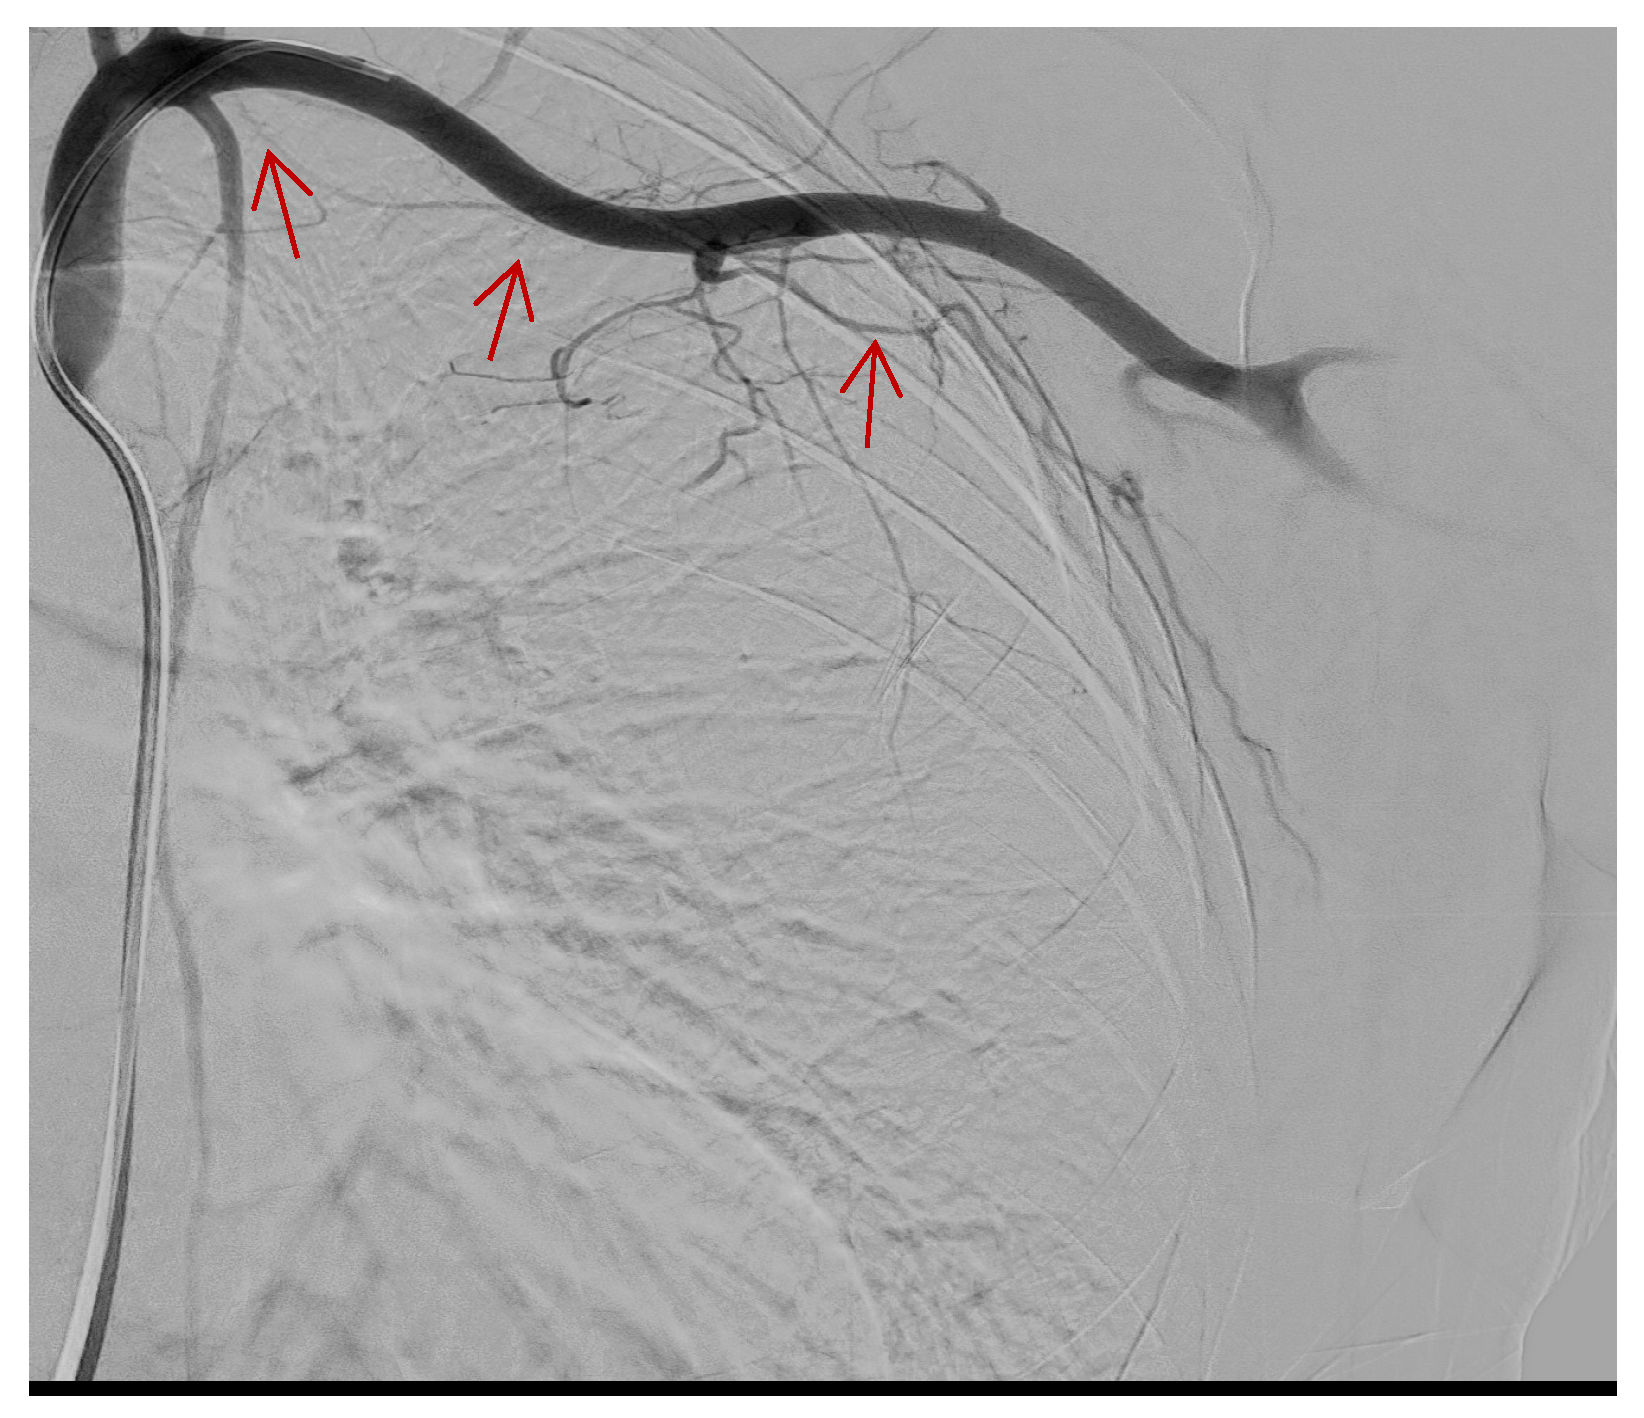

The emergency team was alerted, and endovascular embolization was performed after the patient’s stabilization. The procedure was performed in an emergency, under local anesthesia and anesthetist assistance, with right common transfemoral access (5F) and the selective catheterization of the left subclavian artery.

A preliminary angiographic examination documented the spread of a contrast medium by the distal branch of the lateral thoracic artery, which was embolized by releasing two metal coils (2 mm × 2 cm and 2 mm × 4 cm) (Figure 3 and Figure 4).

Figure 3.

Contrast medium flow in the lateral thoracic artery after selective catheterization of the left subclavian artery. (Red arrows).